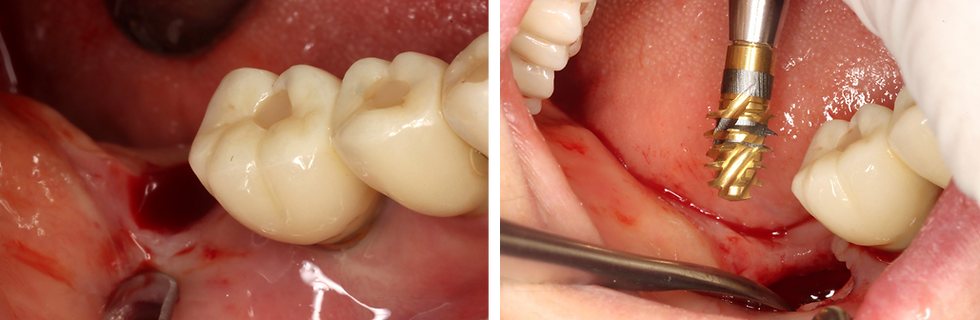

As the implant was removed from an existing site, additional drilling was avoided to prevent unnecessary bone removal.

Prior to implant placement, pre-tapping was performed using the MAXY according to the planned implant depth.

An ALX-IT3 (Ø6.5 × 6.0 mm) implant was placed in bone density D002.